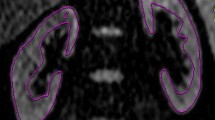

The etiology of CKD is established by the pediatric nephrologist based on clinical and imaging findings as well as pathology reports. Nine patients (45%) had glomerulonephritis, 5 patients (25%) had hemolytic uremic syndrome (Fig. 1), 2 patients (10%) had lupus nephritis, 2 patients (10%) had nepheronophthisis, and 1 patient (1.5%) had infantile nepherosis, whereas the cause of CKD was unknown in one patient (1.5%).

A 20-month-old male child with CKD stage 2, due to typical HUS. a axial T2 WIs of the abdomen showing mildly increased T2 signal intensity. b, c ADC map and measurement of ADC values: right kidney (b) − 1.8, left kidney (c) − 1.7 × 10−3 mm2/s. d, e Color Doppler and spectral wave showing segmental RI of right (d) and left (e) kidney

The stages of CKD were classified according KIDGO guidelines: 6 patients (30%) were stage 1, 4 patients (20%) were stage 2, 3 patients (15%) were stage 3, 2 patients (10%) were stage 4, and 5 patients (25%) were stage 5 (Fig. 2).

A 22-month-old male child with CKD stage 5, due to atypical HUS who underwent plasmapheresis 5 times. a axial and b coronal T2 WIs of the abdomen showing increased parenchymal T2 signal of both kidneys with decreased corticomedullary differentiation. c ADC right kidney = 1.7 × 10 mm /s. d ADC left kidney = 1.6 × 10 mm /s. e Renal Doppler images of right kidney with RI = 0.63